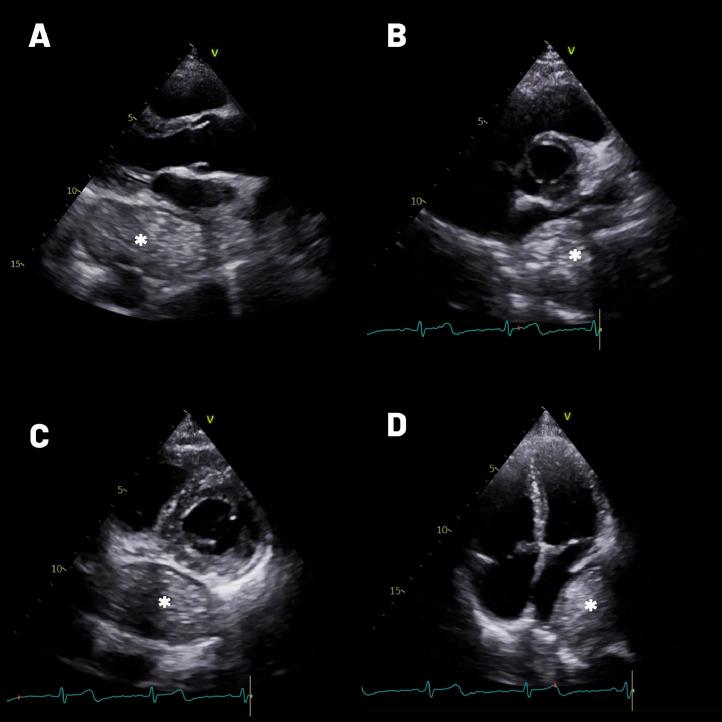

Achalasia is an uncommon disorder affecting esophageal motility. Occasionally, the appearance of a dilated esophagus in achalasia may resemble an extracardiac tumor when observed through transthoracic echocardiography. Left atrial compression due to extensive esophageal dilation is also rare, potentially leading to hemodynamic compromise. Here, we present a rare case involving left atrial compression caused by esophageal dilation in achalasia, with echocardiographic findings mimicking those of an extracardiac tumor.

贲门失弛缓症是一种影响食管动力的罕见疾病。偶尔,通过经胸超声心动图观察时,贲门失弛缓症中扩张的食管外观可能类似于心外肿瘤。由于广泛的食管扩张导致左心房受压也很罕见,可能会导致血流动力学损害。在此,我们报告一例罕见病例,即贲门失弛缓症中食管扩张引起左心房受压,其超声心动图表现类似于心外肿瘤。